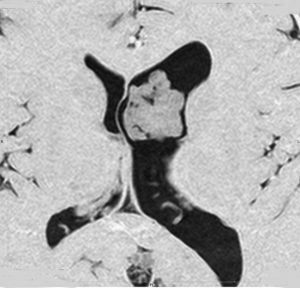

巨大な上衣下腫,でも良性のもの

52歳の男性で,2008年に脳ドックで見つかって無症状でした。中枢性神経細胞種 central neurocytomaを疑いましたが,上衣下腫 subependymomaはまったく考慮に入れませんでした。壮年男性でしたから経過観察しました。右側は2019年,11年後のものです。徐々に増大して水頭症になり歩行障害がでてきました。

手術前の画像です。血管が豊富で大きな導出静脈がみられ,腫瘍内出血もあります。ガドリニウムでは部分的に増強されます。CISS/FIESTAの画像では,透明中核から発生したようにみえて,脳浸潤は全くありません。脳弓は腫瘍の底面にありますが,もちろん境界はっきりしません。これらもcentral neurocytomaの画像所見として捉えられるものです。

transcallosal approach 経脳梁法で亜然摘出しました。底面には脳弓があって剥離できないから全摘出はできません。病理所見は,のう胞形成を伴う線維性基質の中に楕円形の細胞が索状または小巣状に増生するものでsubependymomaと診断されました。異型は軽度で,核分裂像はなく,MIB-1染色率は1%以下のWHO grade Iの所見。EMAは細胞質にdot likeに陽性でしたがわずかであり,ependymomaとの合併腫瘍の診断には至りませんでした。

術後1年の画像です。無症状で復職できています。